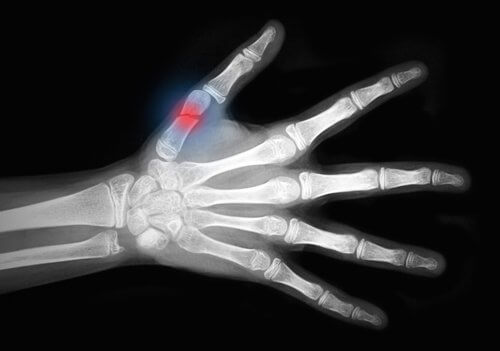

In campo medico per lesioni da sguantamento, o degloving, si intendono le lesioni traumatiche che lacerano i tessuti molli della cute su vaste aree e che espongono l’osso. Interessano, in genere, le estremità.

Le lesioni da degloving richiedono quasi sempre importanti interventi chirurgici. Uno studio pubblicato sul Journal o Emergencies, Trauma and Shock sottolinea l’importanza di un approccio multidisciplinare. Alcune opzioni di trattamento comprendono:

- Reimpianto: consiste nel rimettere insieme parti del corpo che sono state amputate, ad esempio le dita della mano.